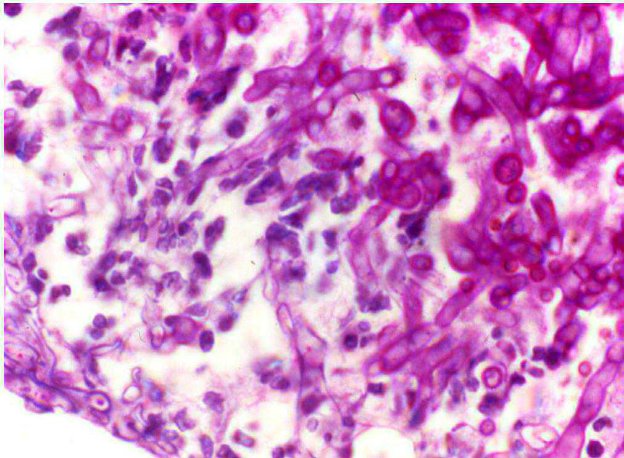

Figura 1 - Colorazione istochimica PAS per evidenziare ife fungine (ben visibili in rosa intenso/fucsa), in un caso di aspergillo si nasale del cane.